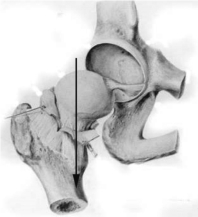

③学习第三类辅助结构——关节唇,给出关节唇的图片,并由图片中的例子详细讲解关节唇的结构特点,及其分布的特征,引导学生由图片特征分析回答出关节唇的主要辅助功能。(学生集体回答)

图4-5-12 肩关节唇

图4-5-13 髋关节唇